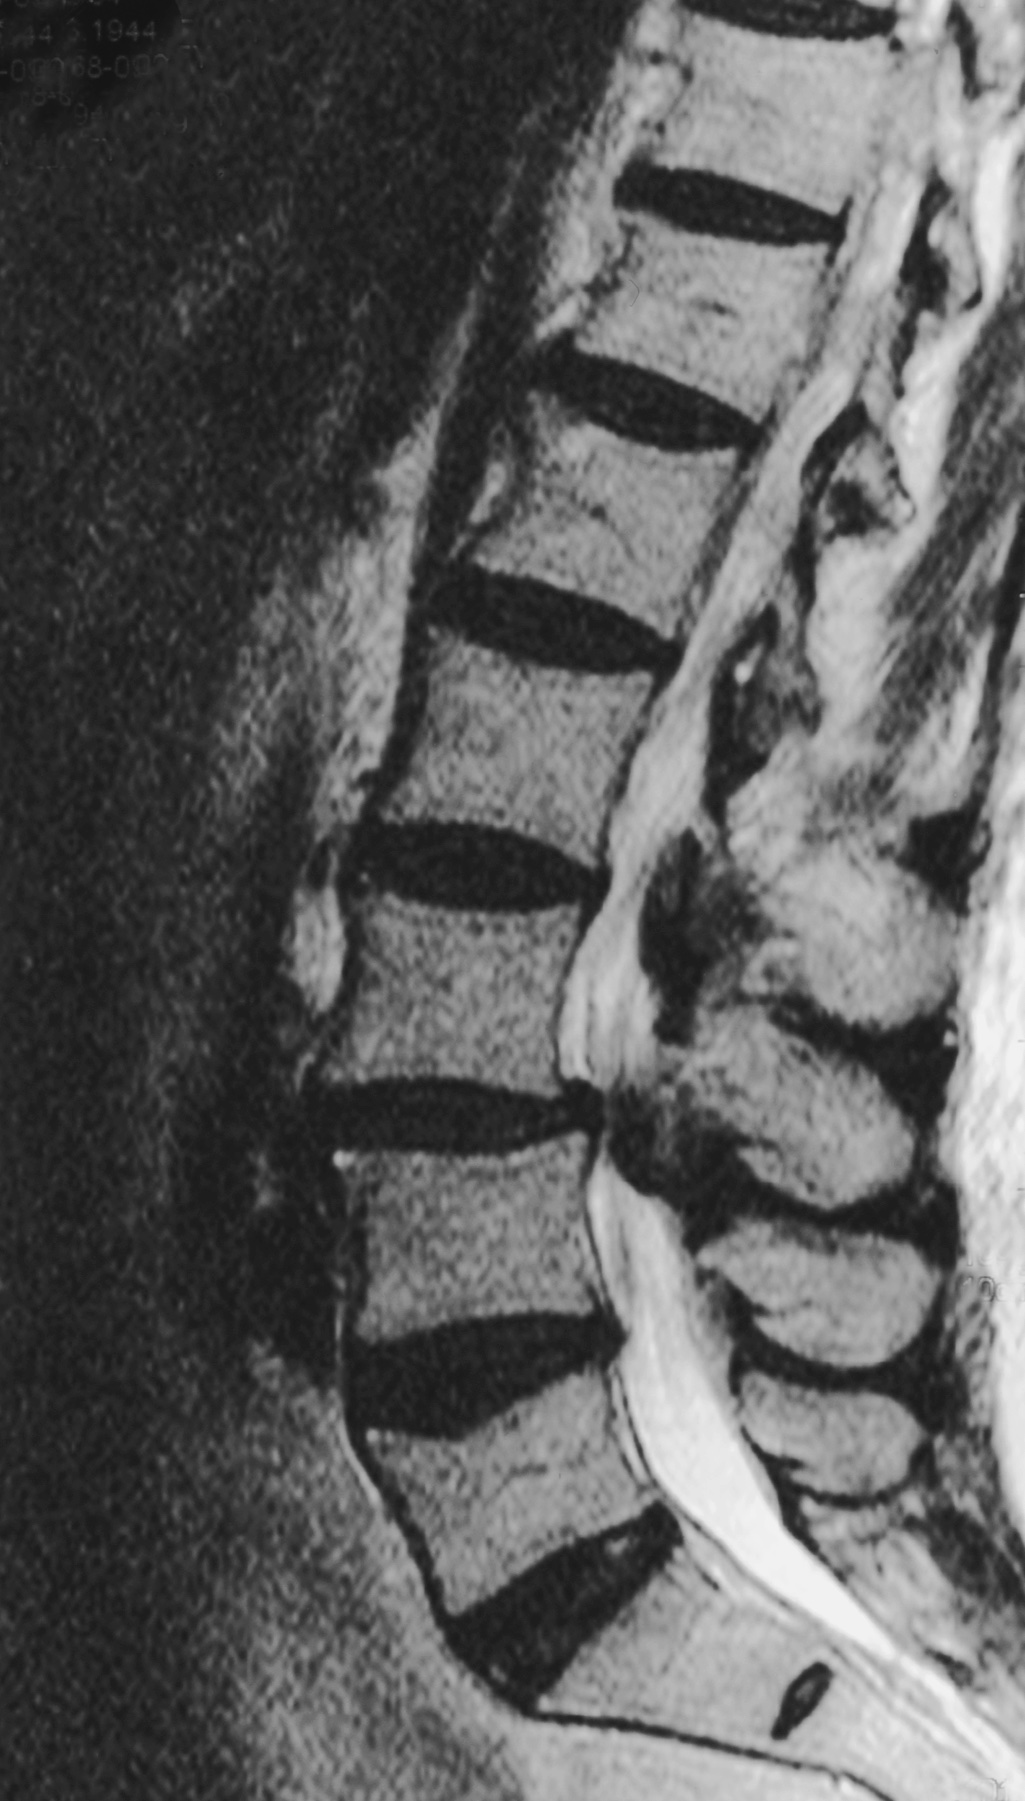

In den meisten Fällen entsteht eine Spinalkanalstenose durch altersbedingte Veränderungen der Wirbelsäule. Mit den Jahren nutzen sich die Bandscheiben ab, es bilden sich kleine Vorwölbungen, und knöcherne Umbauten an Wirbelkörpern oder Wirbelgelenken engen den Wirbelkanal zunehmend ein. So verringert sich der Raum für die Nerven zunehmend, und der Wirbelkanal, in dem das Rückenmark vom Gehirn bis in den oberen Lendenbereich verläuft, verengt sich. Meist sind Patienten betroffen, die das 60. Lebensjahr bereits überschritten haben.

In meiner Praxis setze ich bei der Spinalkanalstenose-OP das mikrochirurgische Verfahren ein. Über einen kleinen Hautschnitt verschaffe ich mir Zugang zu dem Bereich der Wirbelsäule, in dem die Verengung liegt. Unter dem Operationsmikroskop vergrößere ich die betroffenen Strukturen stark und arbeite dadurch besonders präzise.

Im Rahmen dieser sogenannten mikrochirurgischen Dekompression entferne ich kleine Knochenanteile oder verdickte Bänder, die auf Nerven oder Rückenmark drücken. So erweitere ich den Wirbelkanal und stelle den Platz für die Nerven wieder her.

Knochenanteile oder verdickte Bandstrukturen, die die Nerven bedrängen, werden entfernt. Dadurch wird der Wirbelkanal erweitert und die eingeengten Nerven haben wieder mehr Platz.